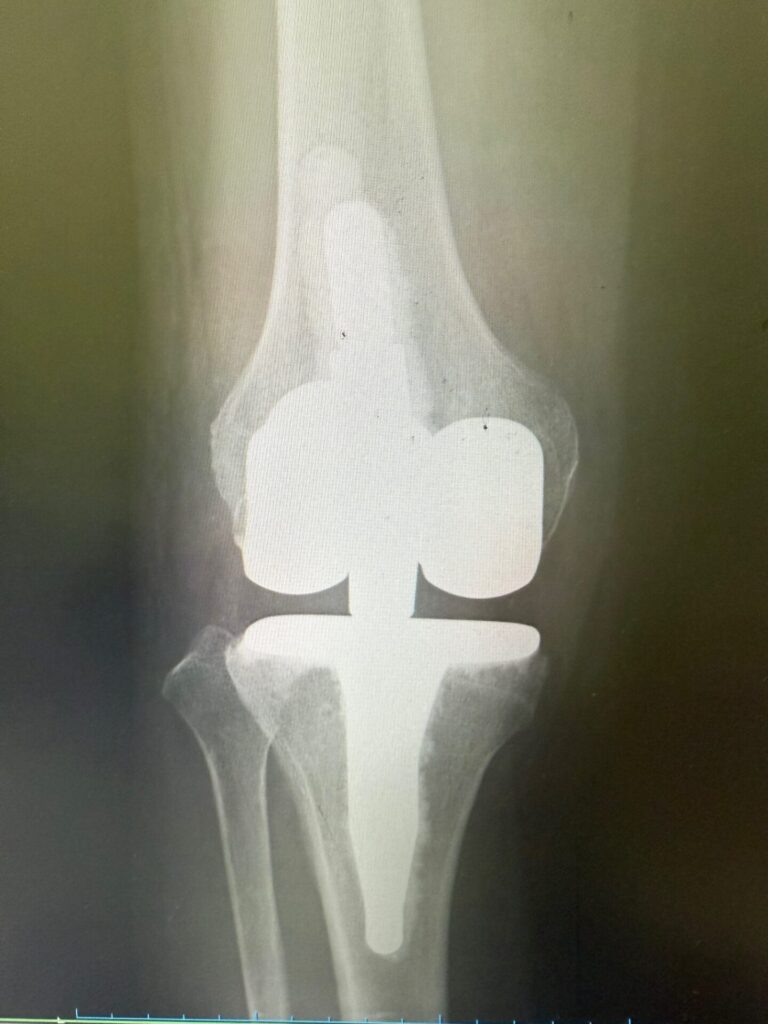

メディカルチェックで、レントゲン上特にヘルニア等の問題はないが、正面像で軽度側弯症、側面像でのアライメント不良判明。

人工膝関節術後の自費リハビリによって更なる日常パフォーマンス向上を希望され会員となられた方。

健康保険での術後回復期リハビリも終えられたが、更なる日常パフォーマンス向上を希望。

メディカルチェックの結果、術後の合併症のためか(?)、腓骨神経麻痺による足関節背屈力低下と腓骨神経領域の軽い痺れ感を認め、日常パフォーマンス向上を妨げる一因となっている可能性も考えられた。クリニックで経過観察しながらフィットネス開始。